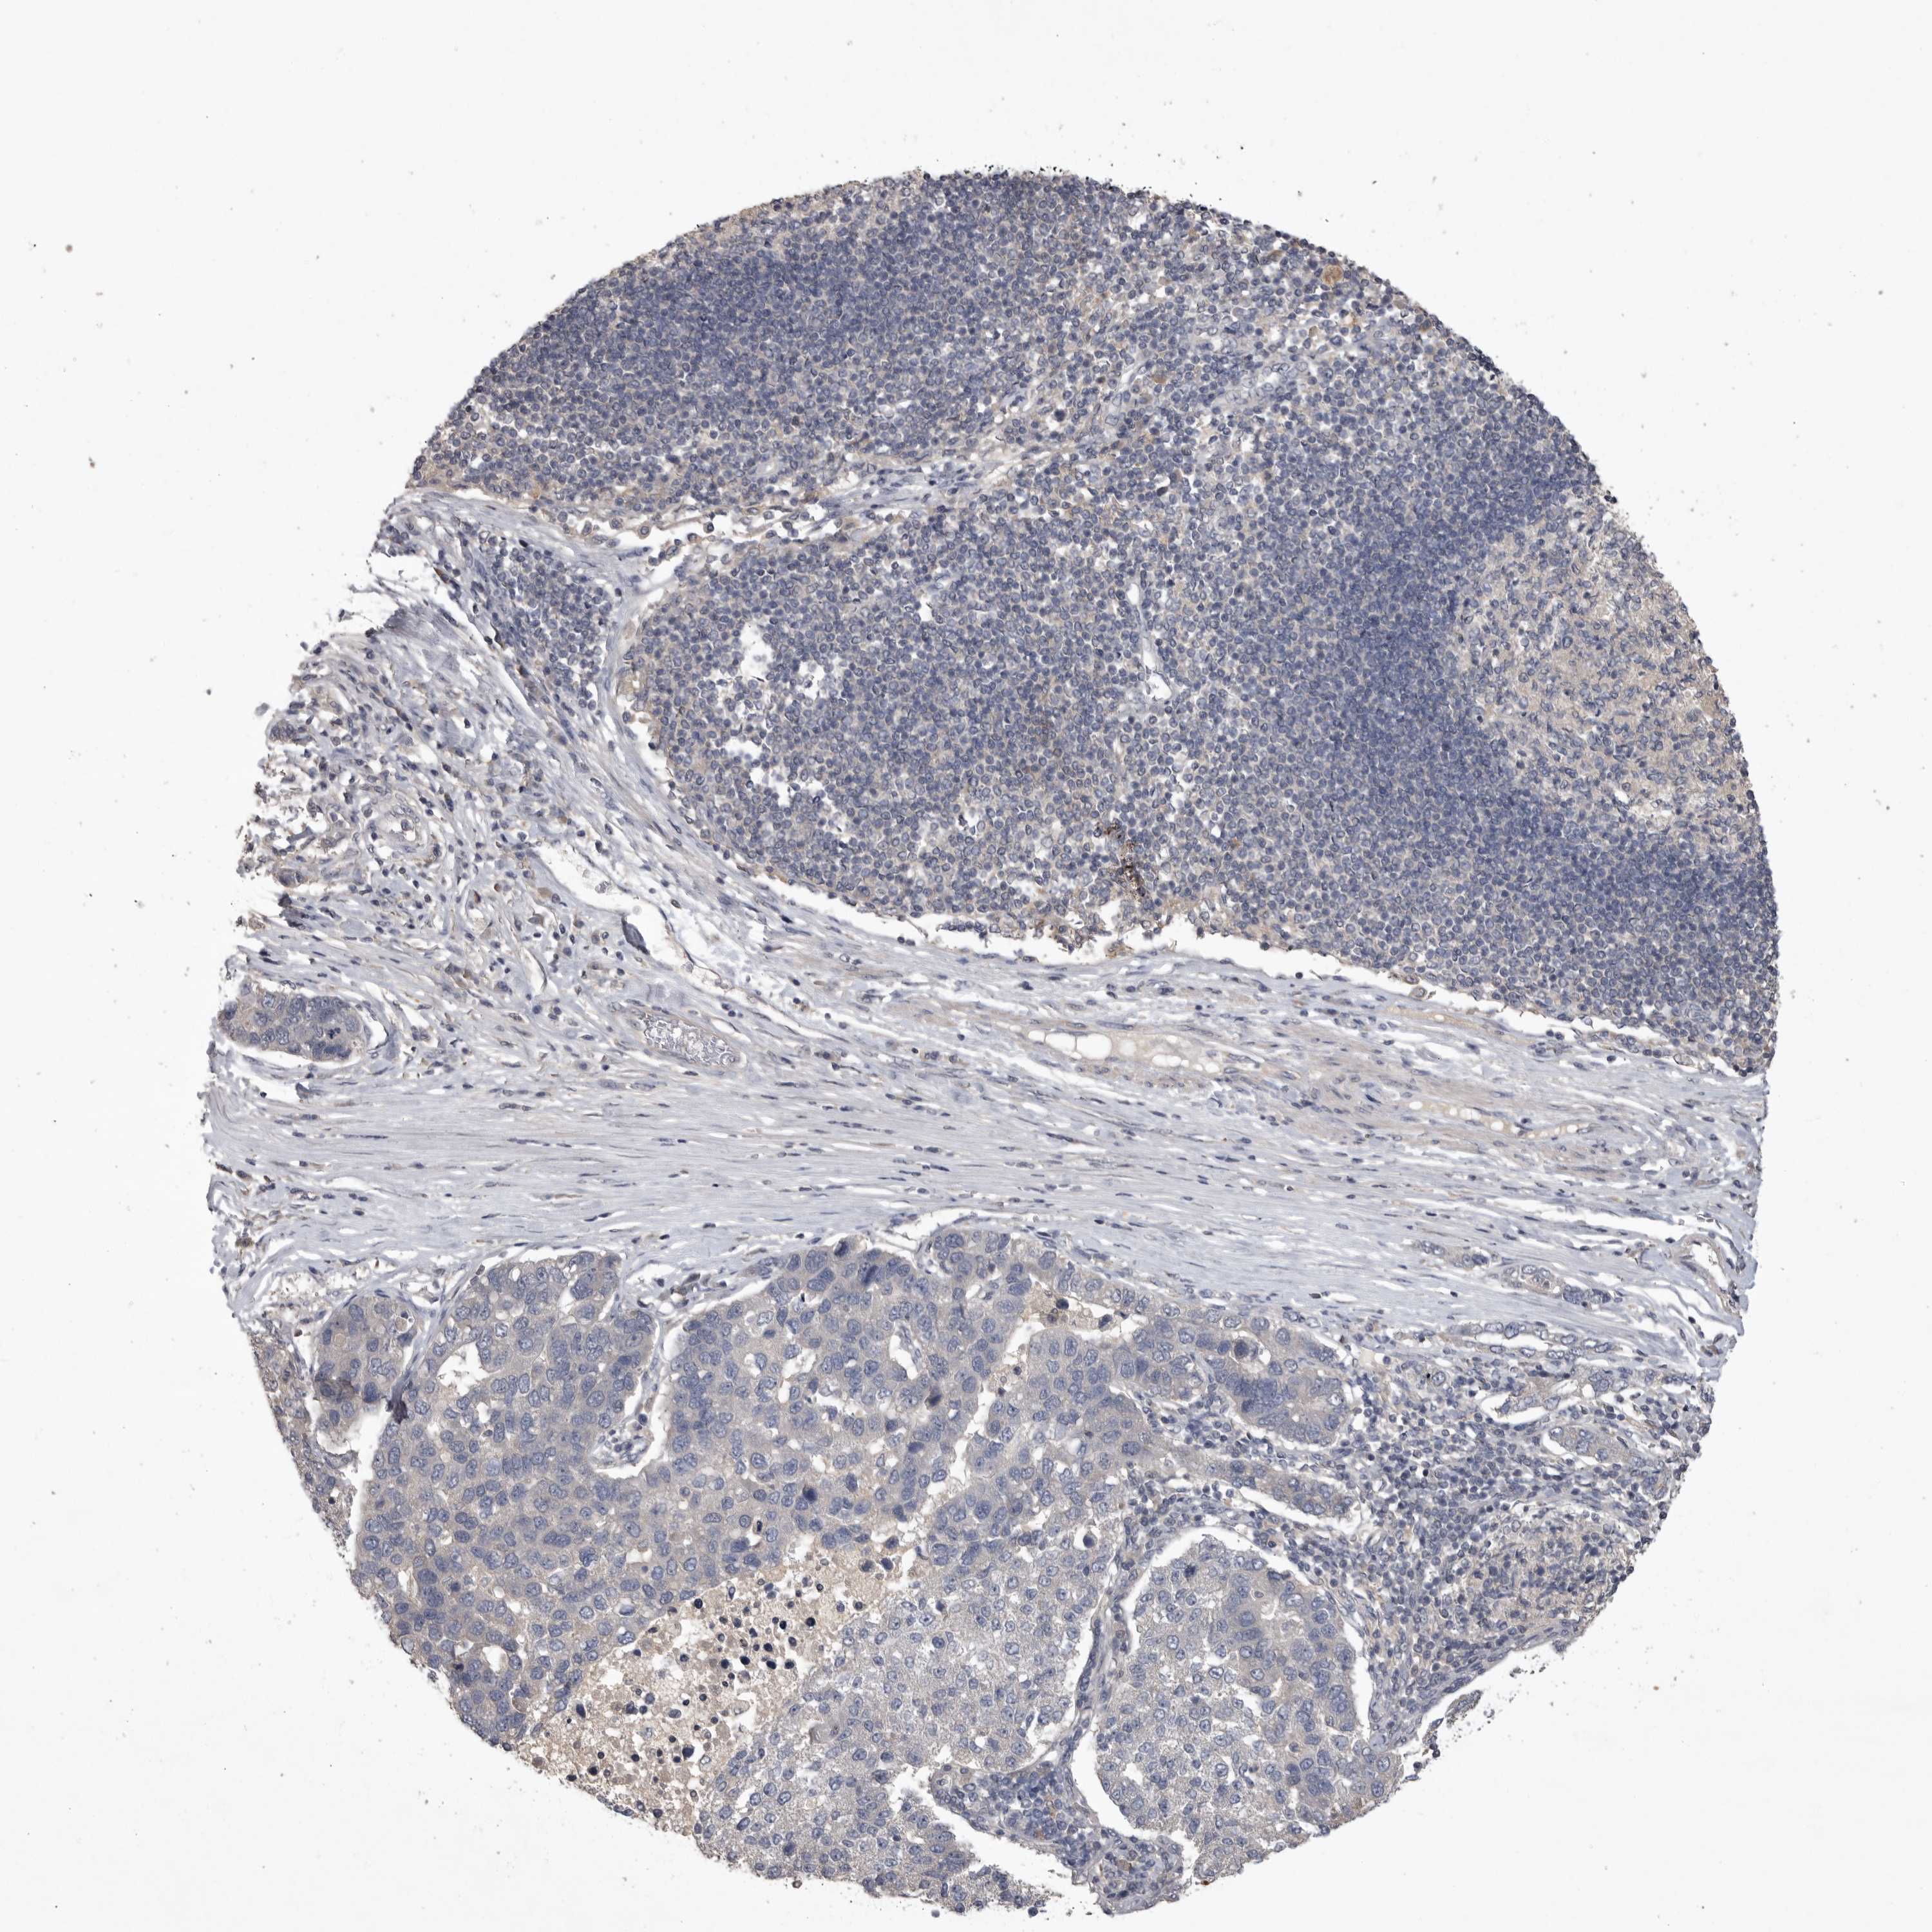

PANCREATIC CANCER - Protein expressioni

A mouse-over function shows sample information and annotation data. Click on an image to view it in a full screen mode. Samples can be filtered based on level of antibody staining by selecting one or several of the following categories: high, medium, low and not detected. The assay and annotation is described here.

Note that samples used for immunohistochemistry by the Human Protein Atlas do not correspond to samples in the TCGA dataset.

Antibody stainingi

Antibody staining in the annotated cell types in the current human tissue is reported as not detected, low, medium, or high, based on conventional immunohistochemistry profiling in selected tissues. This score is based on the combination of the staining intensity and fraction of stained cells.

Each image is clickable and will lead to virtual microscopy that enables deeper exploration of all samples and also displays staining intensity scores, fraction scores and subcellular localization as well as patient and tissue information for each sample.

Antibody HPA025019

Antibody HPA029553

Adenocarcinoma, NOS